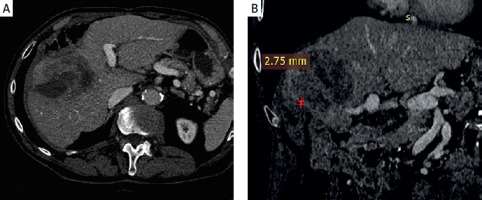

Figure 1

A – Baseline contrast-enhanced axial computed tomography (CT) with a 9.7 cm colorectal liver metastasis. B – Baseline contrast-enhanced coronal CT with the distance from the colon

Ethics board approval for preparation of this case report was waived. A 74-year-old male patient with a history of rectal cancer and synchronous right lobe liver metastases underwent initial treatment with three lines of chemotherapy, a liver wedge resection, and a lower anterior resection. Three years later, a 9.7 cm right lobe colorectal liver metastasis (CLM) was identified, approximately 2.75 mm from the colon (Figure 1). The patient was referred to interventional radiology for consideration of locoregional therapy.